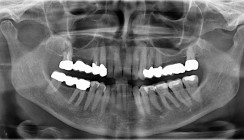

Bisher hatte ich einige Fälle, bei denen der Luxator LX hilfreich gewesen ist. Nach meiner Erfahrung sollte dieses Instrument in Kombination mit anderen Instrumenten aus der Luxator-Reihe verwendet werden. Eine typische Extraktion mit Luxator LX beginnt mit der sorgfältigen Untersuchung des Falls, der Anamneseerhebung des Patienten und der Bewertung des Röntgenbildes. Anschließend wird eine Lokalanästhesie vorgenommen und dem Patienten erklärt, was er während der Behandlung zu erwarten hat. Der Luxator LX wird nun bis zum Widerstandspunkt mit einer mittleren Geschwindigkeit um den gesamten Zahn herum verwendet, um die Wurzelhaut zu durchschneiden. Danach kommen die Luxator Forte Instrumente zum Einsatz, um den Zahn etwas mehr zu lockern. Wenn die Zahnkrone erhalten werden kann, werden passende Zangen verwendet, insbesondere für das vertikale Anheben des Zahns. Wenn nur eine Wurzel übrig bleibt, wird die spezielle Pinzette RootPicker verwendet. Bei Bedarf werden eine Exkochleation und eine Reinigung des Zahnfachs durchgeführt. Es folgt das Einfügen einer Tamponade mit Verbandsmull oder eines equinen Kollagenpflocks. Nach einer Woche wird der Patient zur Nachbehandlung einbestellt.